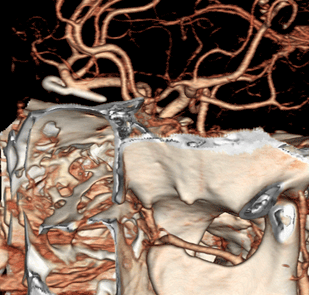

수술전 CT혈관조영술에서 전교통동맥의 비파열성 뇌동맥류 발견

혈관내 코일색전술 후 동맥류 내부에 코일이 들어가 있는 모습